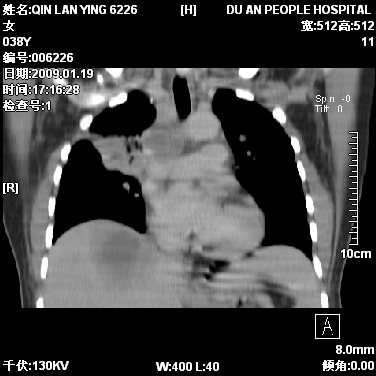

女,38岁,胸疼1个月。wbc:1万4

1)右肺中央型肺癌并右肺上叶阻塞性肺炎、节段性肺不张,纵隔淋巴结转移、右侧胸膜转移、肝脏转移。2)右侧胸腔少量积液。

本病例有几个容易诊断的地方:1、右肺上叶前段支气管闭塞,肺不张。2、淋巴结明显肿大。3、肝脏多个类圆形低密度影呈“牛眼征”改变,高度提示转移。

从影像学角度分析      右肺上叶中央型肺癌,并阻塞性不张、肺炎,纵隔淋巴结、膈顶淋巴结转移。

肝内两个大小不等低密度结节,内可见更低密度影,首先考虑肝内转移瘤,但联想到患者wbc1万4,建议楼主还是做个增强比较明确,除外肝脓肿的可能。